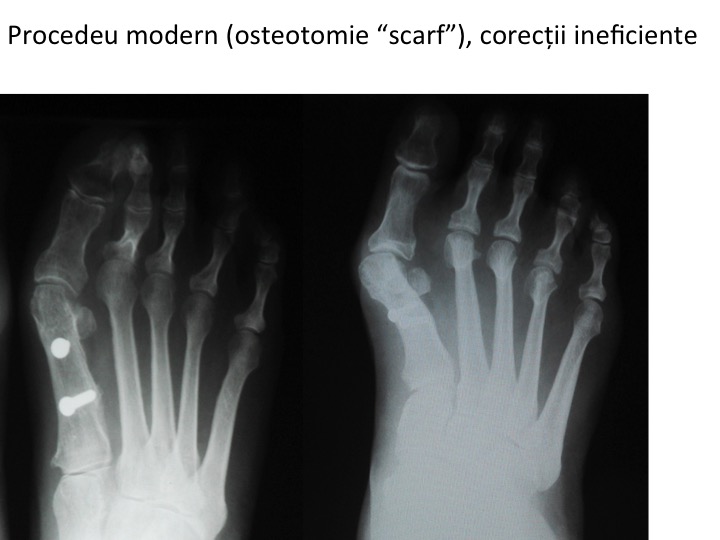

2. HIPO-CORECTIA

- primul metatarsian ramane proeminent, iar halucele ramane deplasat catre lateral, in pozitie de valgus;

- poate fi urmarea unei tehnice chirurgicale moderne, insa aplicata necorespunzator (scarf, chevron etc);

- translatia insuficienta a metatarsianului 1 este cauza cea mai frecventa a hipo-corectiei;

- tehnicile moderne, aplicate necorespunzator (insuficient), pot determina recidiva deformatiei ;

- osteotomia metatarsianului 1 (scarf, chevron etc) produce hipo-corectie in cazul translatiei insuficiente a fragmentelor;